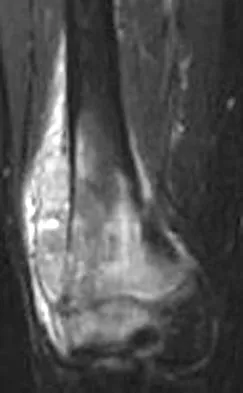

A 37-year-old woman has had intermittent paresthesias and numbness in the plantar foot for the past 6 months. She reports that the symptoms are worse with activity, and the paresthesias are beginning to awaken her at night. MRI scans are shown in Figures 6a and 6b. What is the most likely diagnosis?

Explanation

The symptoms are consistent with tarsal tunnel syndrome. Ganglion cysts are a well-known cause of tarsal tunnel syndrome. The MRI scans show a high intensity, well-circumscribed mass in the tarsal tunnel that is consistent with a fluid-filled cyst. Patients usually respond well to excision of the ganglion and resolution of the tarsal tunnel symptoms. The surrounding fat is a different signal intensity on the MRI scans, which rules out a lipoma. Synovial cell sarcoma has a heterogeneous appearance on an MRI scan. Metastatic tumors are most commonly found in the osseous structures of the foot, not the soft tissues. Rozbruch SR, Chang V, Bohne WH, et al: Ganglion cysts of the lower extremity: An analysis of 54 cases and review of the literature. Orthopedics 1998;21:141-148. Llauger J, Palmer J, Monill JM, et al: MR imaging of benign soft-tissue masses of the foot and ankle. Radiographics 1998;18:1481-1498.